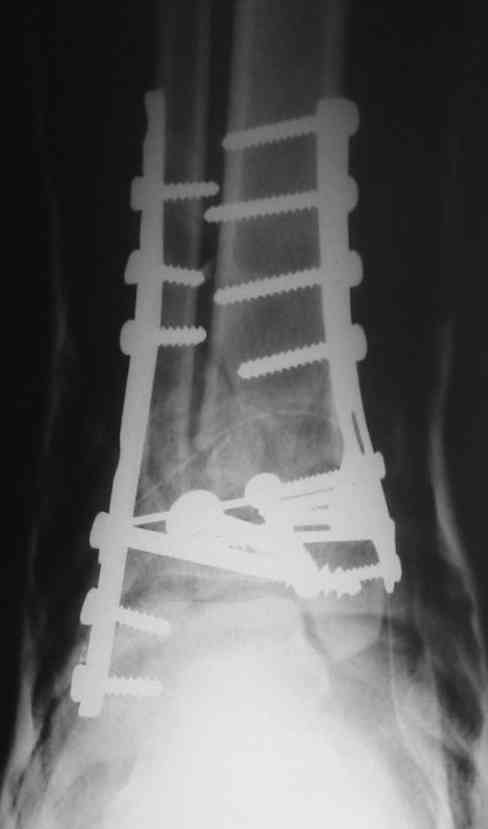

OK, Dr Driagin, Ja operiroval bolnogo po Vashemu, hotia sam ni ochen' ubezden' v itom, t.k. bolnoi otkazalsa na proch' ot ex.fix, ja emu sdelal ORIF + Kostnia plastika, snimky prelogiottsa,

Очень прилично получилось, но мне показалось, что винты на 4,5 мм.Это принципиально винты используются 3,5 и 4,0 мм. И проекцию прямую бы переделать. С уважением Дрягин

ДВ> И проекцию прямую бы переделать.

А зачем ее переделывать?

На представленном снимке видно, что эпифиз смещен латерально.

Сейчас с этим ничего не сделать, похоже.

Однозначно сказать сложно.Расстояние между тараном и медиальной лодыжкой меньше чем между тараном и крышей большеберцовой кости.Это может быть за счёт не правильной укладки.Пока не отчаиваетесь.Главное вы поняли принцип.Сделайте несколько проекций прямых и посмотрим.Для всех интересно.С уважением

Мне кажется, что все конечно далеко от идеала. Сложный перелом. Есть ощущение, что малоберцовая кость (ключ!) фиксирована с ротацией и удлинением. Снимки конечно необходимо сделать в правильных проекциях и без гипса...

В голеностопном суставе обязательны 3 стандартные ренгенологические проекции: прямая, латеральная и мортиз. Без них невозможно трактовать состояние голеностопа.